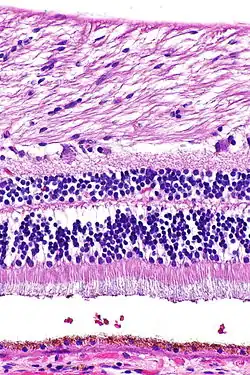

Retina (part of the eye) stained with hematoxylin and eosin, cell nuclei stained blue-purple and extracellular material stained pink

H&E is the combination of two histological stains: hematoxylin and eosin. The hematoxylin stains cell nuclei a purplish blue, and eosin stains the extracellular matrix and cytoplasm pink, with other structures taking on different shades, hues, and combinations of these colors.[5][6] Hence a pathologist can easily differentiate between the nuclear and cytoplasmic parts of a cell, and additionally, the overall patterns of coloration from the stain show the general layout and distribution of cells and provides a general overview of a tissue sample's structure.[7] Thus, pattern recognition, both by expert humans themselves and by software that aids those experts (in digital pathology), provides histologic information.

Hematoxylin principally colors the nuclei of cells blue or dark-purple,[6][15][14] along with a few other tissues, such as keratohyalin granules and calcified material. Eosin stains the cytoplasm and some other structures including extracellular matrix such as collagen[5][7][14] in up to five shades of pink.[8] The eosinophilic (substances that are stained by eosin)[5] structures are generally composed of intracellular or extracellular proteins. The Lewy bodies and Mallory bodies are examples of eosinophilic structures. Most of the cytoplasm is eosinophilic and is rendered pink.[10][15] Red blood cells are stained intensely red.